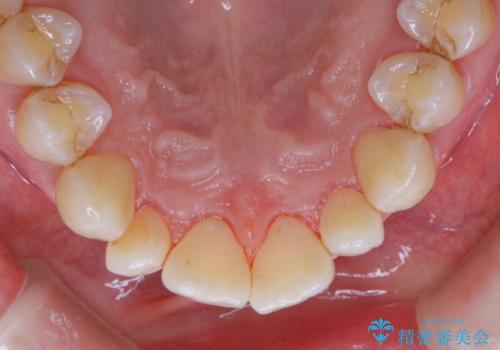

- かなり久しぶりの来院とのことで、クリーニング希望でした。全体的に汚れの付着があったため、PMTCの60分コースを行いました。

PMTCとは、プロフェッショナル・メカニカル・トゥース・クリーニングという、専門家による機械的な歯のクリーニングです。 PMTCは、歯磨きだけでは落とすことのできない細菌・バイオフィルムを除去することが目的です。

歯の健康を守るためには、1回だけで終わらすことなく、定期的にPMTCを行うことがとても大切です。